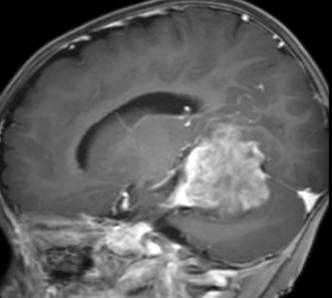

入院后,患儿头颅MRI平扫+增强提示:右侧小脑幕上下骑跨巨大肿瘤,压迫右侧丘脑、侧脑室、脑干、小脑等重要结构,考虑胚胎型肿瘤可能性大。肿瘤与周围组织无明显边界,手术难度极大、风险极高。

脑肿瘤术前2